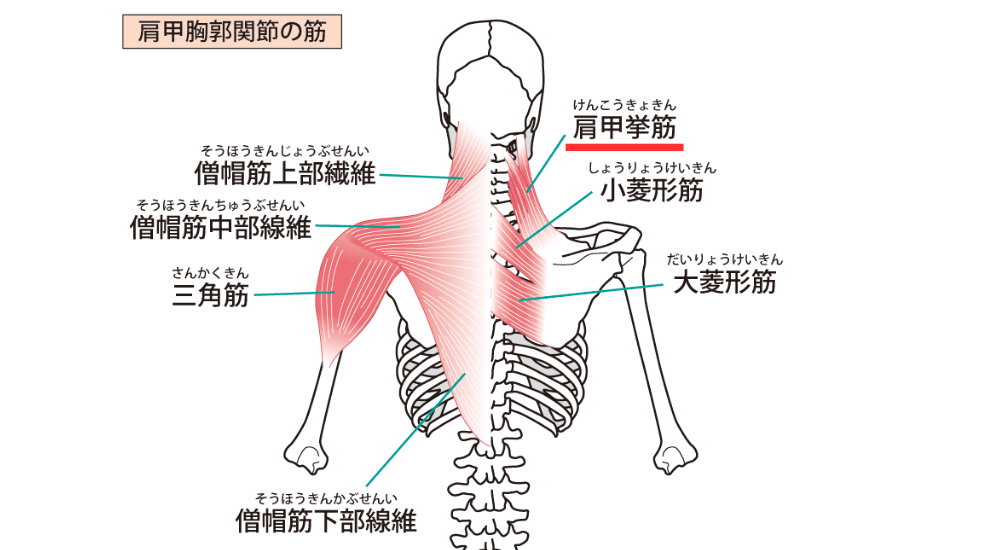

- 僧帽筋(上部)・肩甲挙筋: 首から肩にかけての筋肉。ストレートネックや猫背で頭部を支えるために過剰に緊張し、肩凝りや首の痛みの原因となります。

- 菱形筋: 肩甲骨と背骨の間。猫背で引き伸ばされて硬くなり、肩甲骨内側の凝りや痛みの原因となります。